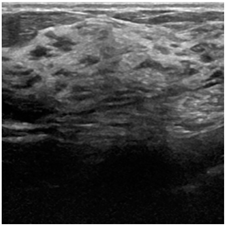

| Benign | Malignant | Normal | |

|---|---|---|---|

| BU images | ![]() | ![]() | ![]() |

| Number of images per class | 437 | 210 | 133 |